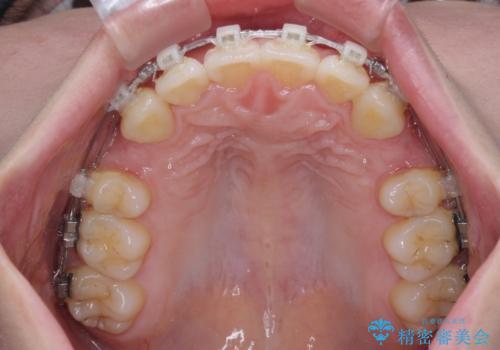

- 矯正装置

- クリアブラケット

- 1年10ヶ月

- 下唇に跡がつくほどに飛び出した上顎前歯を気にして来院された患者様です。

来院された時から4本の抜歯が必要であることを理解されていらしており、通法通り上下左右の第一小臼歯4本を抜歯し、ワイヤー装置にて矯正治療を行うこととしました。

順調に治療が進み、2年弱で想定していたとおりの仕上がりにて治療を終えることができました。